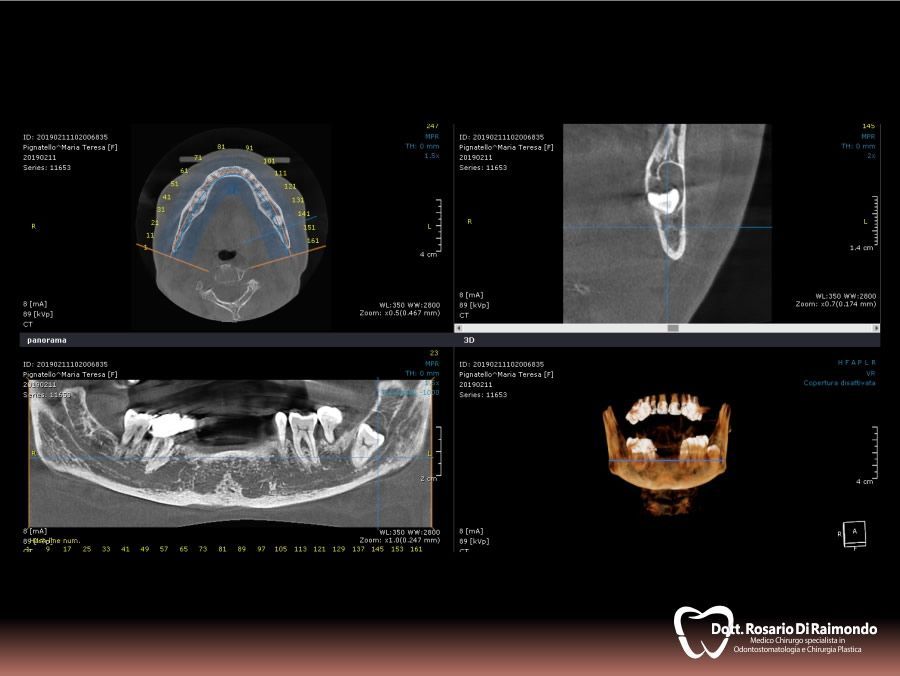

Casi Trattati

Di seguito riportiamo alcune fotografie di casi esplicativi di Chirurgia Orale.